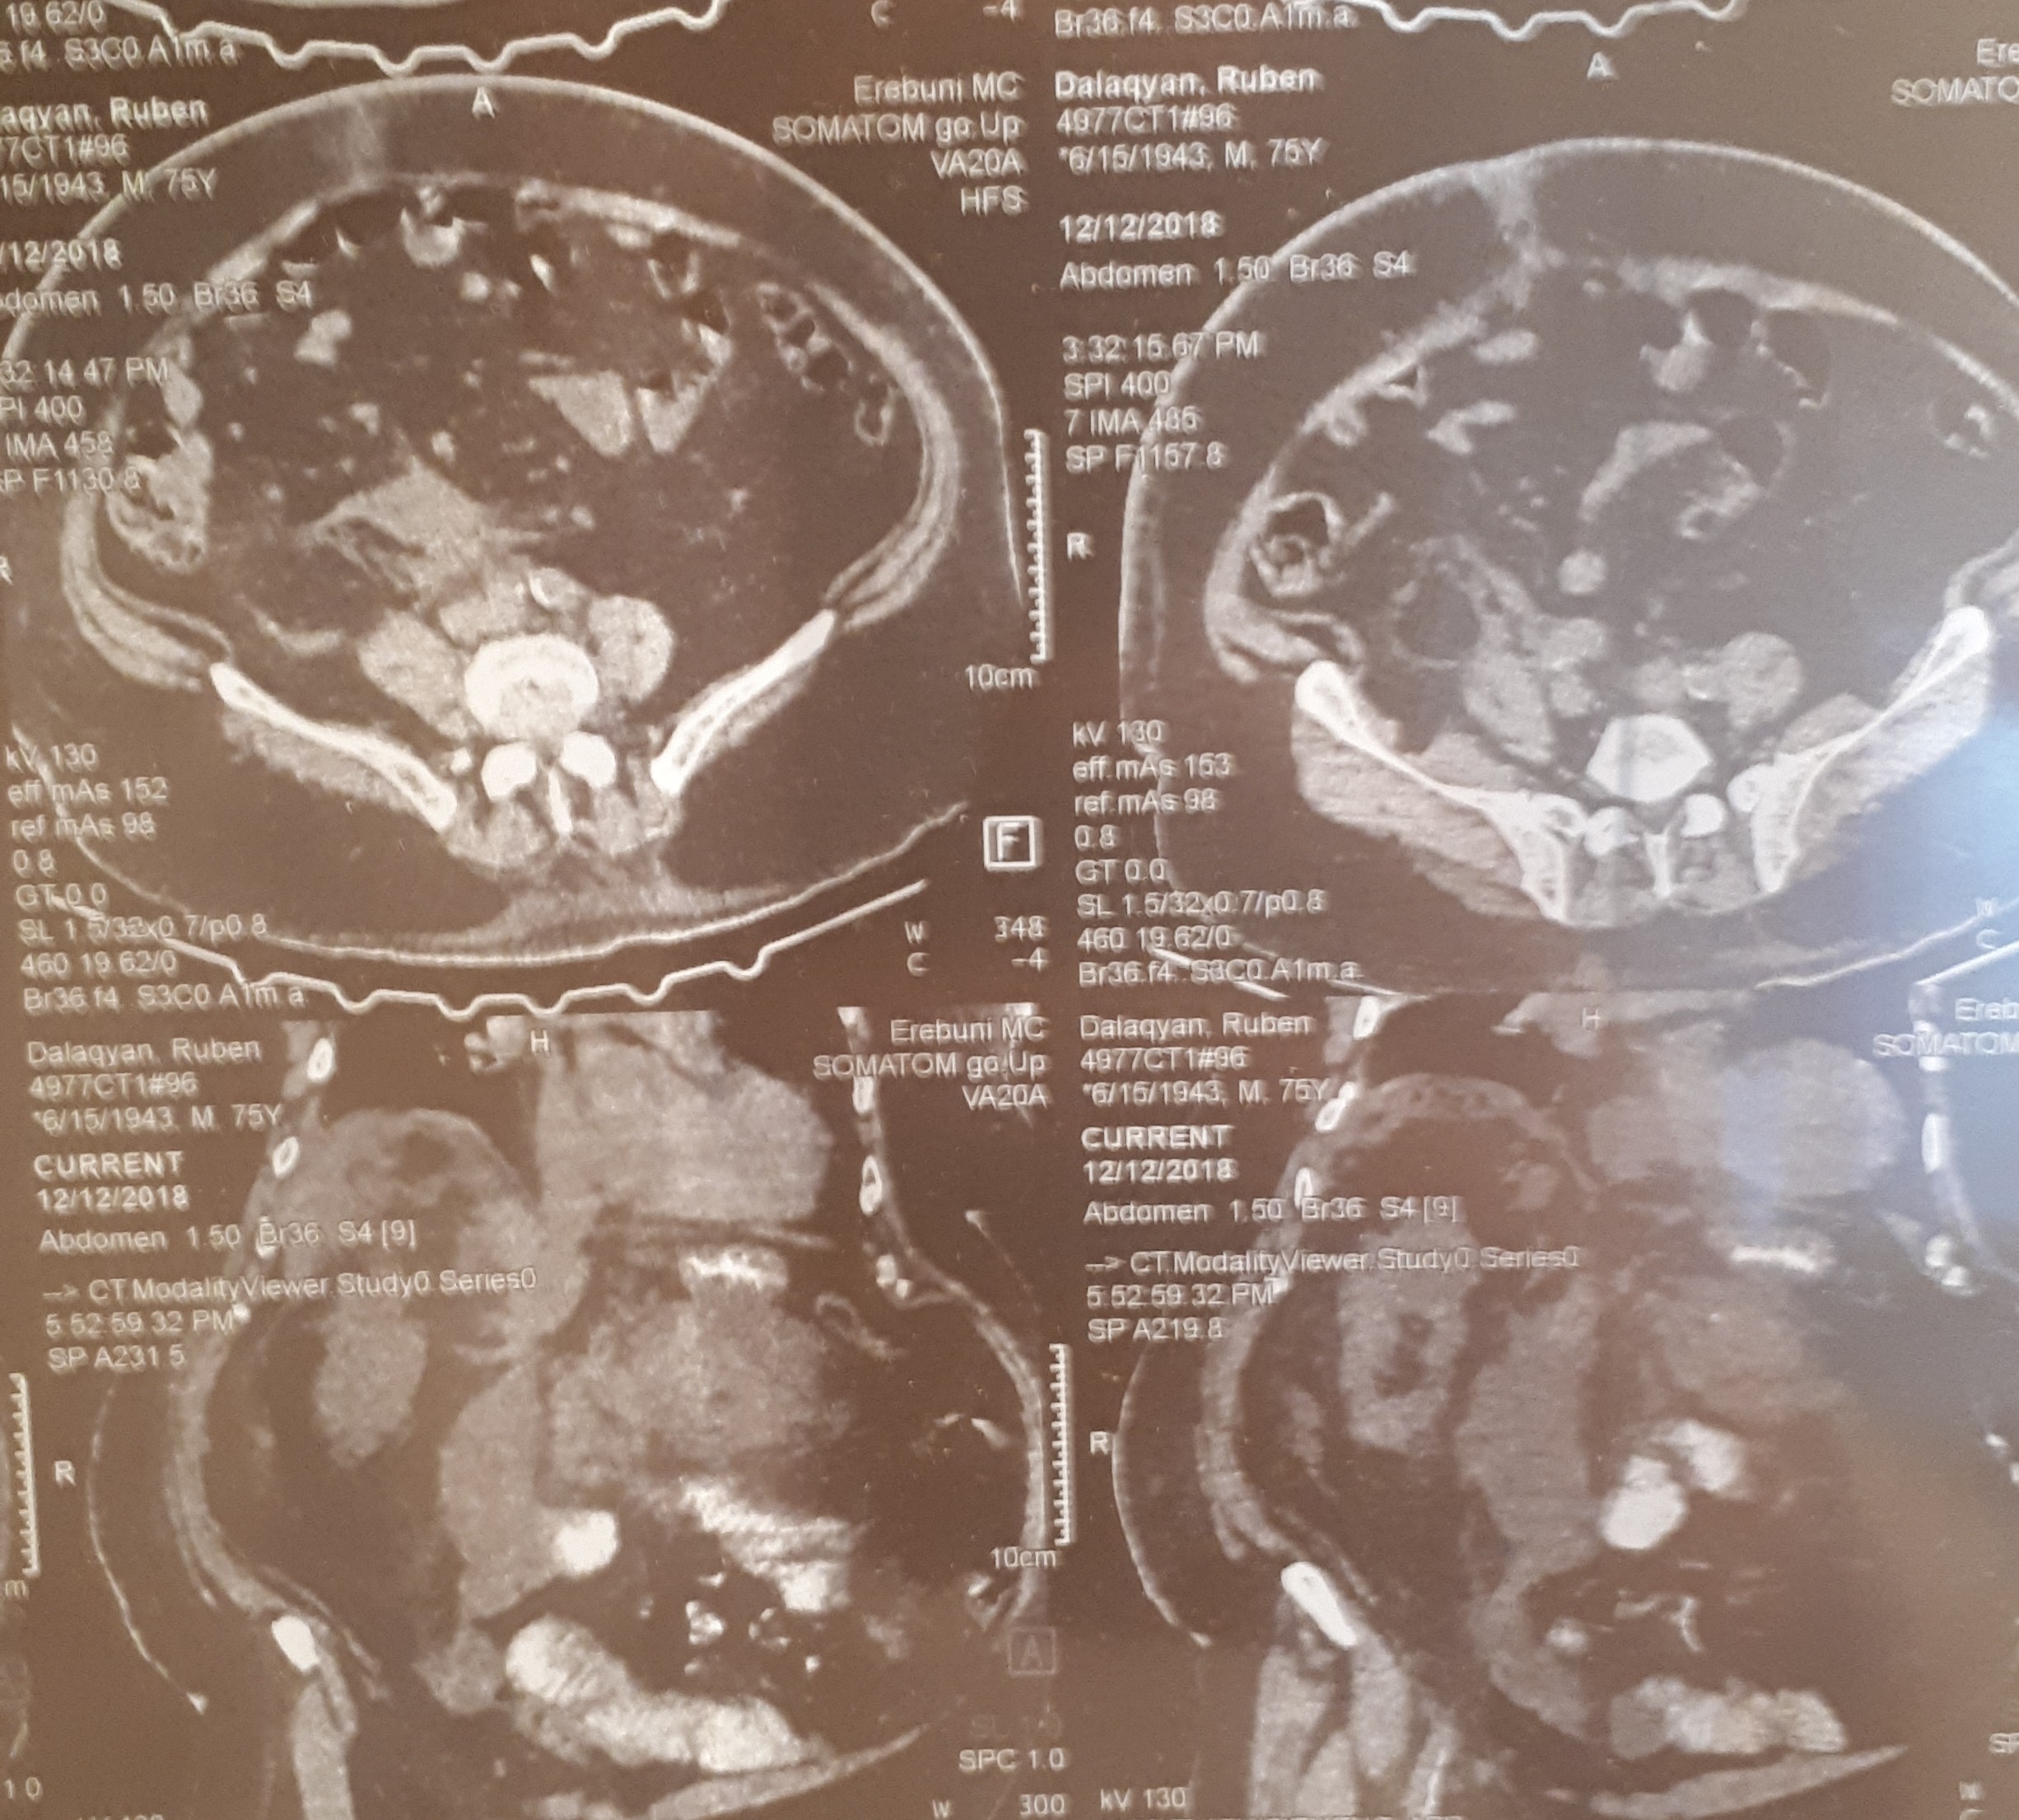

տղամարդը եւ հիպերտենզիա ԱՓՇ-ում…Այս խնդիրների դեպքում բաց վիրահատությունը ուղղակի հակացուցված է: Արա Վարդանյանը ընտրել է այլ ճանապարհ: Առաջին հերթին՝ տեղային անզգայացման պայմաններումուլտրաձայնայինհսկողությամբ իրականացվել է հետորովայնամզային տարածության թարախակույտի դրենավորում, հաջորդ օրը կատարվել է ճարպոնային ծոցի դրենավորում: Սահմանվել է դինամիկ հսկողություն եւ կոնսերվատիվ թերապիա: Ինֆուզիոն, հակաբակտերիալ, սիմպտոմատիկ թերապիան շարունակվել է վիրաբուժական բաժանմունքում: Սրանով, սակայն, բուժումը չի ավարտվել: Մի քանի օր անց դրենավորվել է նաեւ աջից ենթադիաֆրագմալ տարածությունում առկա թարախակույտը: Հիվանդը ստոցիոնարում բուժումը շարունակել է եւս մի քանի օր եւ դուրս գրվել հիվանդանոցից բավարար վիճակում, ճարպոնային ծոցի եւ հետորովայնամզային տարածության գործող դրենաժներով: Նա, իհարկե, կշարունակի մնալբժշկի հսկողության տակ, բայց վերադարձել է նախկին կենսակերպին, ցավային զգացողություններ չունի: